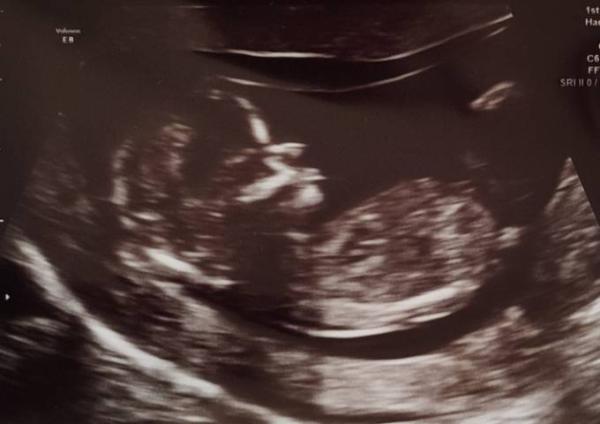

Ich komme gerade vom Ersttrimester Screening. Laut Ultraschall ist alles bestens. Alles voll in der Norm. Am Freitag ist die Auswertung vom Bluttest da... es ist wirklich sehr erleichternd sowas zu hören....Unser Würmchen hat geschlafen und die Beine so schön angewinkelt dass nicht zu sehen war was es werden könnte, aber das ist im Moment auch nicht wichtig....

Bild zu Entwicklung zeitgerecht und unauffällige NT - Forum für Juli - Mamis